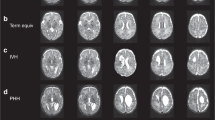

Fibre tractography of the PLIC and CC

DTI datasets were analysed on an off-line workstation using commercially available processing software as provided by the manufacturer (FiberTrak, by Philips Medical Systems, Best, the Netherlands). DTI colour-coded maps were automatically computed, red representing a right-left, green an anterior-posterior and blue a superior-inferior orientation. These colour-coded DTI maps were used to place a single seed to perform fibre tracking using an automated 3D seeded algorithm. First, for the PLIC in the axial plane at the level of the lateral ventricles and subsequently for the genu and splenium of the CC in the mid-sagittal plane regions of interest were defined. The seed was placed as is shown in Fig. 1. Position changes of the seed-point in the structure of interest resulted in identical fibre tracts, indicating the robustness of the method used. Two investigators (FTdB and AvS, blinded to subject’s age and degree of WM injury) identified the regions of interest and manually placed the individual seeds in consensus for each region of interest. Subsequently, fibre tracts were generated through the PLIC and the callosal genu and splenium resulting in visualisation of fibres (Fig. 2). The quality of all tracts was visually assessed in order to minimise erroneous pathways, which were erased and not used in further analyses. In all analyses, default settings were used consisting of a minimum FA of 0.15, a maximum angle change of 27.0 degrees and a minimum fibre length of 10.0 mm. We used the manufacturer default settings, since (small) changes of these settings, to optimize the performance of the fibre tracking, did not have any influence on the fibres picked by the tracking routine. Finally FA and ADC values of these fibre bundles were obtained and the length of the fibres was calculated.

a-b: Fibre tracts in an infant undergoing imaging at PMA of 41 weeks a through the PLIC and b through the genu and splenium of the CC using an automated 3D seeded technique according to default settings (FiberTrak, Philips Medical Systems, Best the Netherlands; minimum FA 0.15, maximum angle change 27.0 degrees, minimum fibre length 10.0 mm)